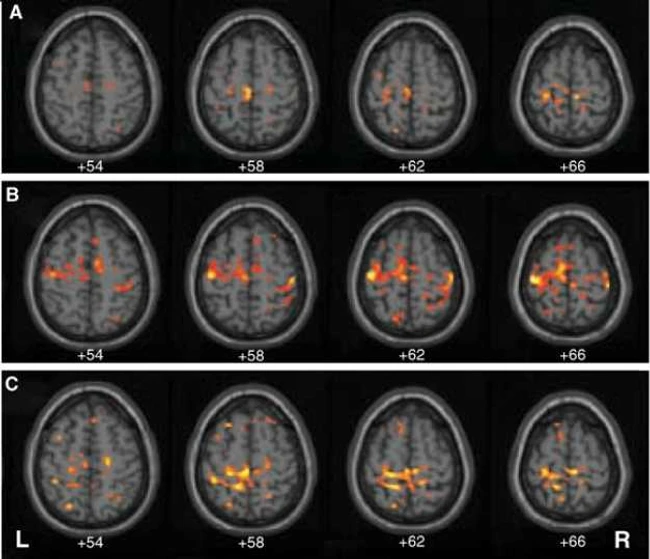

Pentru a observa diferenţele după cele 14 zile de stil de viaţă sănătos, cercetătorii au realizat investigaţii înainte şi după cele două săptămâni asupra creierului participanţilor, prin comparaţie cu creierul unui grup de control (care nu a beneficiat de aceleaşi modificări în modul de trai).

Rezultatele au fost surprinzătoare chiar şi pentru oamenii de ştiinţă americani care au realizat studiul: persoanele din grupul de intervenţie au demonstrată o fluenţă verbală net superioară grupului de control după cele 14 zile.

„De asemenea, am observat o reducere cu 5% a activităţii din cortexul prefrontal dorsolateral, o zonă cerebrală a cărei activitate poate «umbri» activitatea din zonele responsabile cu memoria. De altfel, s-a dovedit că activitatea redusă în cortexul prefrontal dorsolateral reflectă o mai mare eficienţă a ariei cerebrale implicată în memoria de lucru (n. r. – memoria pe termen scurt, care permite să ne amintim, de exemplu, fraza pe care tocmai am citit-o)“, relatează Gary Small, coordonatorul cercetării.